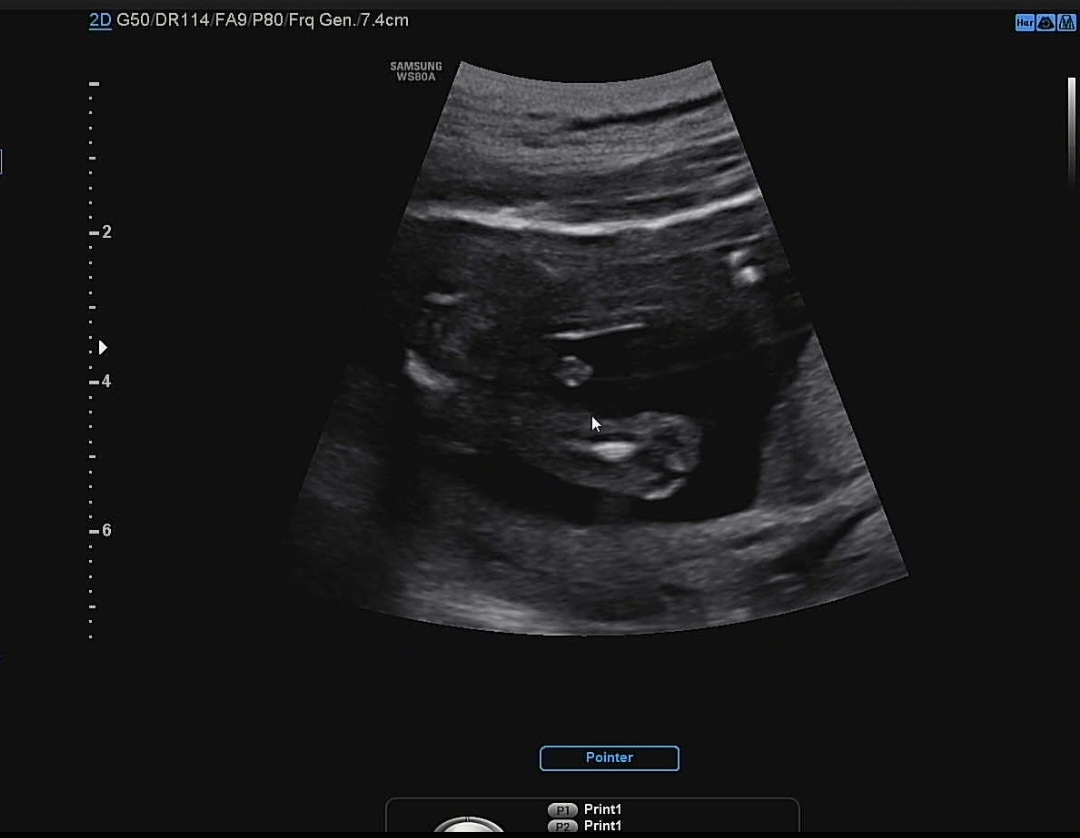

성별 초음파사진봐주세여

16주 3일에 봤는데 이거 빼박 아들인거져??

의사선생님은 저거 보시자 마자 아들이네요~ 라고 하셨었어여!! 탯줄일 확률도 있는거네여🙊

오..좀 헷갈려요 꼬추랑 다리랑 거의 이어져 있는데 저건 몬가 탯줄 같기도 하구요!